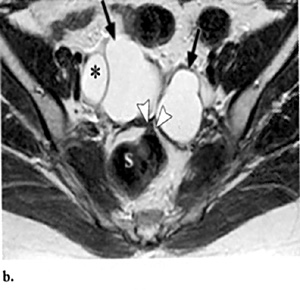

H μαγνητική τομογραφία (MRI) έχει αποδειχθεί ως ένα χρήσιμο μη επεμβατικό διαγνωστικό μέσο της ενδομητρίωσης. H μαγνητική τομογραφία υπερέχει της υπερηχογραφίας στην ενδομητρίωση του περιτοναίου, η οποία εμφανίζεται ως πολλαπλά μικρά οζίδια, γιατί μπορεί να ανιχνεύσει την ύπαρξη ενδομητριωσικών εμφυτεύσεων στις Τ1 ακολουθίες με ευαισθησία 11-27% και με σήμα το οποίο ποικίλει σε ένταση ανάλογα με την ενεργό δραστηριότητα και τη χρονική διάρκεια της βλάβης. Στις Τ2 ακολουθίες οι εμφυτεύσεις εμφανίζονται ως μάζες χαμηλού σήματος λόγω της αντιδραστικής ίνωσης που περιβάλλει τις μικρές συλλογές ενδομητριωσικού υλικού, αν και κάποιες φορές στο εσωτερικό των εμφυτεύσεων μπορεί να υπάρχει υψηλής έντασης σήμα λόγω της κυκλικής αιμορραγίας (εικόνα 2). Όταν όμως οι λήψεις της μαγνητικής τομογραφίας λαμβάνονται με καταστολή του λίπους, βελτιώνεται η ανίχνευση των ενδομητριωσικών εμφυτεύσεων στο περιτόναιο, αυξάνοντας την ευαισθησία της μεθόδου στο 47-61% και την ειδικότητα στο 87-97%.

Επιπλέον, στη μαγνητική τομογραφία οι συμφύσεις εμφανίζονται ως χαμηλής έντασης σήματος νηματοειδείς σχηματισμοί, οι οποίοι καθιστούν ασαφείς τις διαχωριστικές επιφάνειες δύο παρακείμενων οργάνων και μπορούν ενίοτε να προσλαμβάνουν σκιαστικό, χωρίς ωστόσο να αυξάνουν την ευαισθησία ή την ειδικότητα της μαγνητικής τομογραφίας. Σύμφωνα με μελέτη των Katayama και συν. εκτιμήθηκε η αξία της μαγνητικής τομογραφίας στην εκτίμηση των πυελικών συμφύσεων χρησιμοποιώντας μια ειδική τεχνική και διαπιστώθηκε πως η ευαισθησία και η ειδικότητα της μεθόδου είναι 72.5% και 87.4% αντίστοιχα. Η οπίσθια κλίση και καθήλωση της μήτρας στον δουγλάσειο, η προσκόλληση των ωοθηκών μεταξύ τους και στην οπίσθια επιφάνεια της μήτρας, η γωνίωση των εντερικών ελίκων, η ανύψωση των οπίσθιων κολπικών θόλων, η εγκυστωμένη συλλογή υγρού και η παρουσία υδροσαλπίγγων αποτελούν έμμεσα ευρήματα, ενδεικτικά συμφύσεων (εικόνα 3).(15,16)

Η μαγνητική τομογραφία έχει αποδειχθεί χρήσιμη στη διάγνωση των ενδομητριωμάτων, με ευαισθησία και ειδικότητα συγκρίσιμη, και σύμφωνα με κάποιους ερευνητές, μεγαλύτερη της διακολπικής υπερηχογραφίας, αλλά σαφώς και με μεγαλύτερο κόστος ως εξέταση. Συγκεκριμένα ο Takahashi διαπίστωσε πως τόσο η κλασική, όσο και η μαγνητική τομογραφία με καταστολή του λίπους ανιχνεύει όλα σχεδόν τα ενδομητριώματα με διάμετρο μεγαλύτερη των 10 χιλιοστών.(17) Ακόμη η νόσος μπορεί να βρίσκεται σε αρχικό στάδιο, όταν η μαγνητική τομογραφία ανιχνεύει βλάβες μικρότερες των 6 χιλιοστών, ενώ βλάβες μεγαλύτερες των 15 χιλιοστών συσχετίζονται με προχωρημένο στάδιο.(18) Στην κλασική μαγνητική τομογραφία τα ενδομητριώματα εμφανίζονται ως πολλαπλές, ομοιογενείς, υψηλού σήματος μάζες στις Τ1 ακολουθίες και με χαμηλής έντασης σήμα στις Τ2 ακολουθίες ως «σκιά» λόγω της αποδόμησης των προϊόντων του αίματος και της δημιουργίας αιμοσιδηρίνης. Όμως σε περίπτωση πρόσφατου ενεργού ενδομητριώματος η παρουσία αίματος και στις δύο, Τ1 και Τ2, ακολουθίες θα εκδηλώνεται ως υψηλής έντασης σήμα, γεγονός που καθιστά δύσκολη τη διαφοροδιάγνωση από τις αιμορραγικές κύστεις των ωοθηκών. Επίσης, το παχύ ινώδες τοίχωμα της ενδομητριωσικής κύστης εμφανίζεται ως χαμηλής έντασης σήμα στις Τ2 ακολουθίες, με πρώιμη πρόσληψη του σκιαστικού εξαιτίας της ύπαρξης αγγείωσης και μακροφάγων με αιμοσιδηρίνη.

Η εν τω βάθει ενδομητρίωση συνήθως απαντάται στη μαγνητική τομογραφία ως ανώμαλου σχήματος οζίδια διαμέτρου έως 25 χιλιοστά με σήμα ίδιας έντασης με το μυομήτριο και διάσπαρτες μικρές εστίες υψηλής έντασης στις Τ1 ακολουθίες, ορατές ακόμη και με καταστολή του λίπους. Στις Τ2 ακολουθίες το σήμα των οζιδίων είναι ίδιας ή μικρότερης έντασης σε σχέση με το σήμα του μυομητρίου, με διάσπαρτες υψηλής έντασης εστίες στο εσωτερικό τους. Συνήθεις θέσεις εντόπισης των οζιδίων αποτελεί το ορθοκολπικό διάφραγμα, με σπάνια επέκταση στα παραμήτρια και τους ουρητήρες, στους ιερομητρικούς συνδέσμους, στην κυστεομητρική πτυχή, στο τοίχωμα του ορθοσιγμοειδούς με χαρακτηριστική εστιακή υπερτροφία του έξω μυικού χιτώνα και εξέλκωση του βλεννογόνου, χωρίς όμως ενδοαυλική επέκταση, σημείο διαφοροδιαγνωστικό από το καρκίνωμα του εντέρου (πίνακας 2).(19)